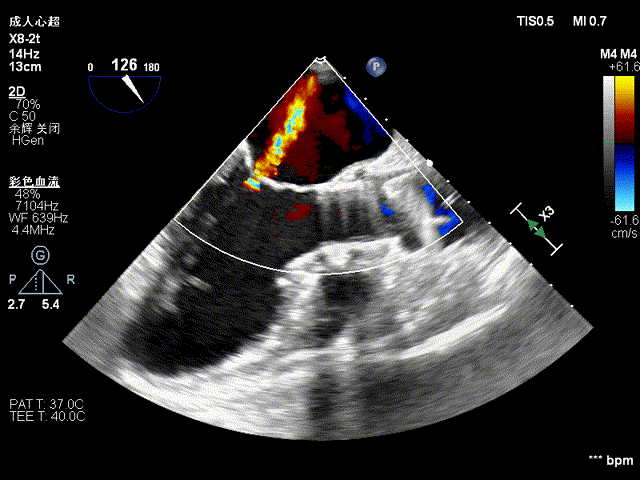

瓣膜快速释放到位后TEE观察患者二尖瓣反流明显减少,左心室收缩功能得到改善,心电监护提示ST段逐渐恢复至正常,心率下降至80次/分,血氧饱和度升至98%,血压逐渐上升到正常,血流动力学趋于稳定。造影观察瓣膜形态、位置良好,无瓣周漏。术后当天拔除气管插管,第二天患者即可下床活动。

瓣膜释放后二尖瓣反流明显减少

释放后即刻评估

目前中南医院TAVR术中多模态影像技术协同指导,术中“超声语言”与“DSA语言”协同,及“以解剖为中心”和“以影像为中心”两种语言的统一(例如超声常用三腔心切面对应为DSA下的RAO+CAU投照角度),可在手术过程中可快速、及时评判并发症、导丝导管的位置等;帮助假体瓣膜更快更直接的定位;术中即刻评估,协助医生快速判断植入的效果,如瓣膜的植入深度与毗邻组织的关系,瓣膜的形态、瓣周漏评估等。